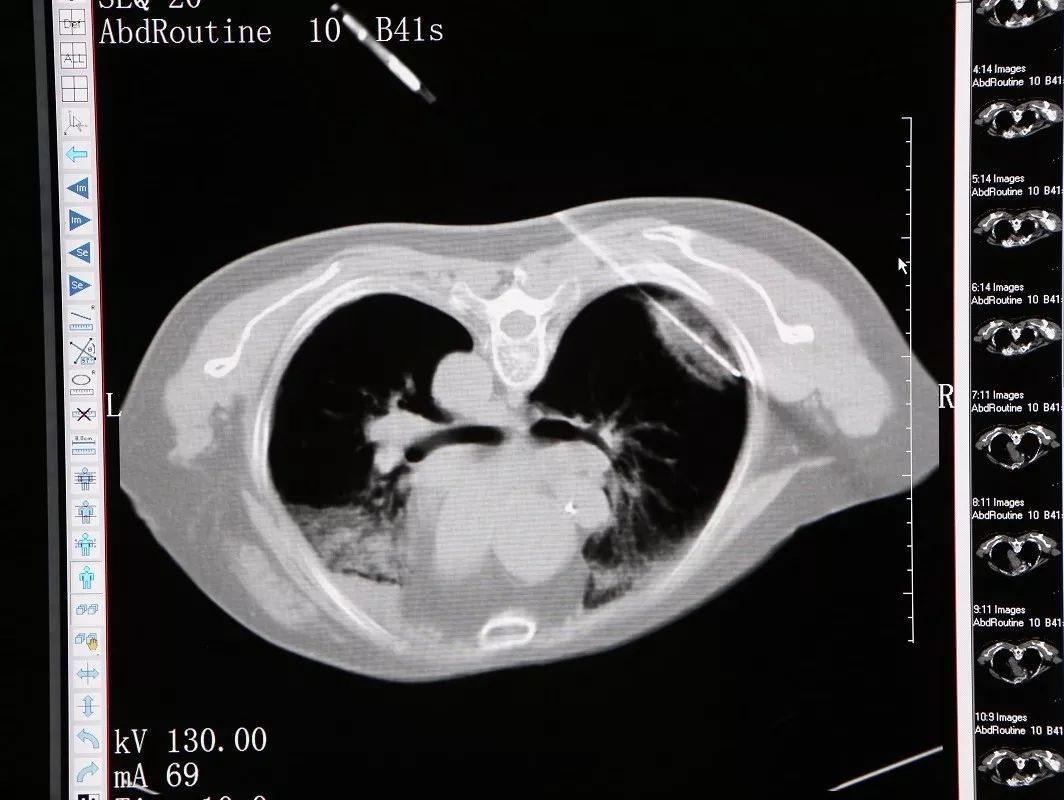

11月26日,穆阿姨被送至微创治疗室在CT引导静脉全麻下行右肺结节氩氦刀冷冻消融术,在实施静脉全麻后,术者将她摆成俯卧位,CT扫描以右肺背段近胸膜处结节为靶区,在CT引导下,用氩气超冷刀经穿刺点准确的穿刺到右肺结节,然后开始实施冷冻。术中通过CT扫描监测冷冻范围和有无并发症的发生,经过两个5分钟的冷冻循环后,CT扫描显示右肺的结节被成功的消融了。CT扫描见冰球覆盖靶区,复温后拔除超冷刀,包扎穿刺点,术中出血2ml,无手术标本,术后麻醉清醒,未诉不适,生命体征平稳。